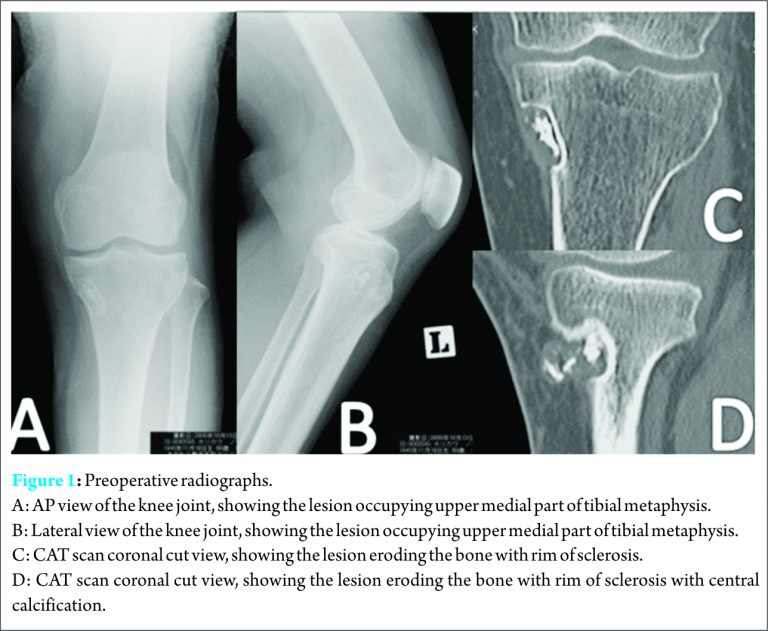

A 73-year-old female presented with a four year history of a painful swelling in the left knee that was slowly growing, with a gradual increase in pain at the same time.. She had unnoticeable medical history. Pain was aggravated by weight bearing, sitting straight, but she enjoyed full range of motion, and her general health was not affected. Osteoarthritis of left knee joint was suspected in another clinic, and she was treated conservatively with analgesic drugs. The pain persisted despite administration of nonsteroidal anti-inflammatory drugs (NSAIDs) for long time; she visited our outpatient clinic for consultation. Clinical examination revealed local tenderness over medial aspect of proximal tibia, small well defined swelling over the medial proximal tibia was palpable. It was firm in consistency and was not red or hot to touch. Roentgenography revealed a small well-defined osteolytic lesion with thinning out of the cortex over medial part of proximal tibia, surrounded by a thin sclerotic margin (Fig.1a,1b). Computed tomography (CT) scan revealed radiolucent lesion eroding the cortex, with central calcification (Fig.1c,1d)